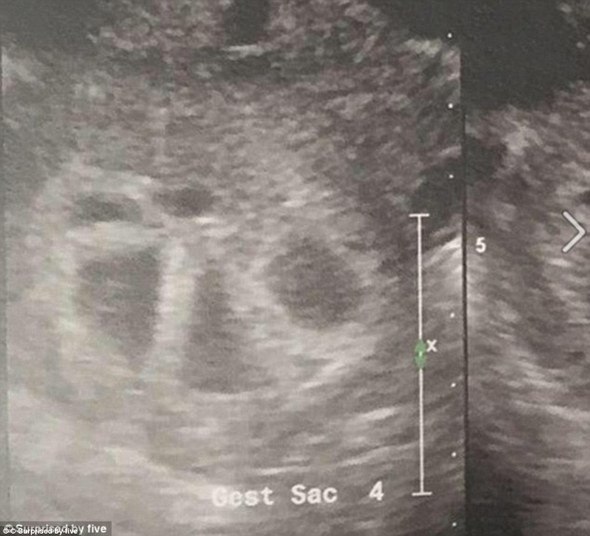

O casal tentava ter filhos desde o início do ano passado. Porém, em julho foram informados que a jovem estava grávida de gêmeos — quando, na verdade, viriam mais três de brinde

Quando ela pediu para usar outra máquina de ultra-som — para que pudesse ter uma visão mais clara dos bebês — o mundo virou de cabeça para baixo: o médico encontrou cinco batimentos cardíacos separados.